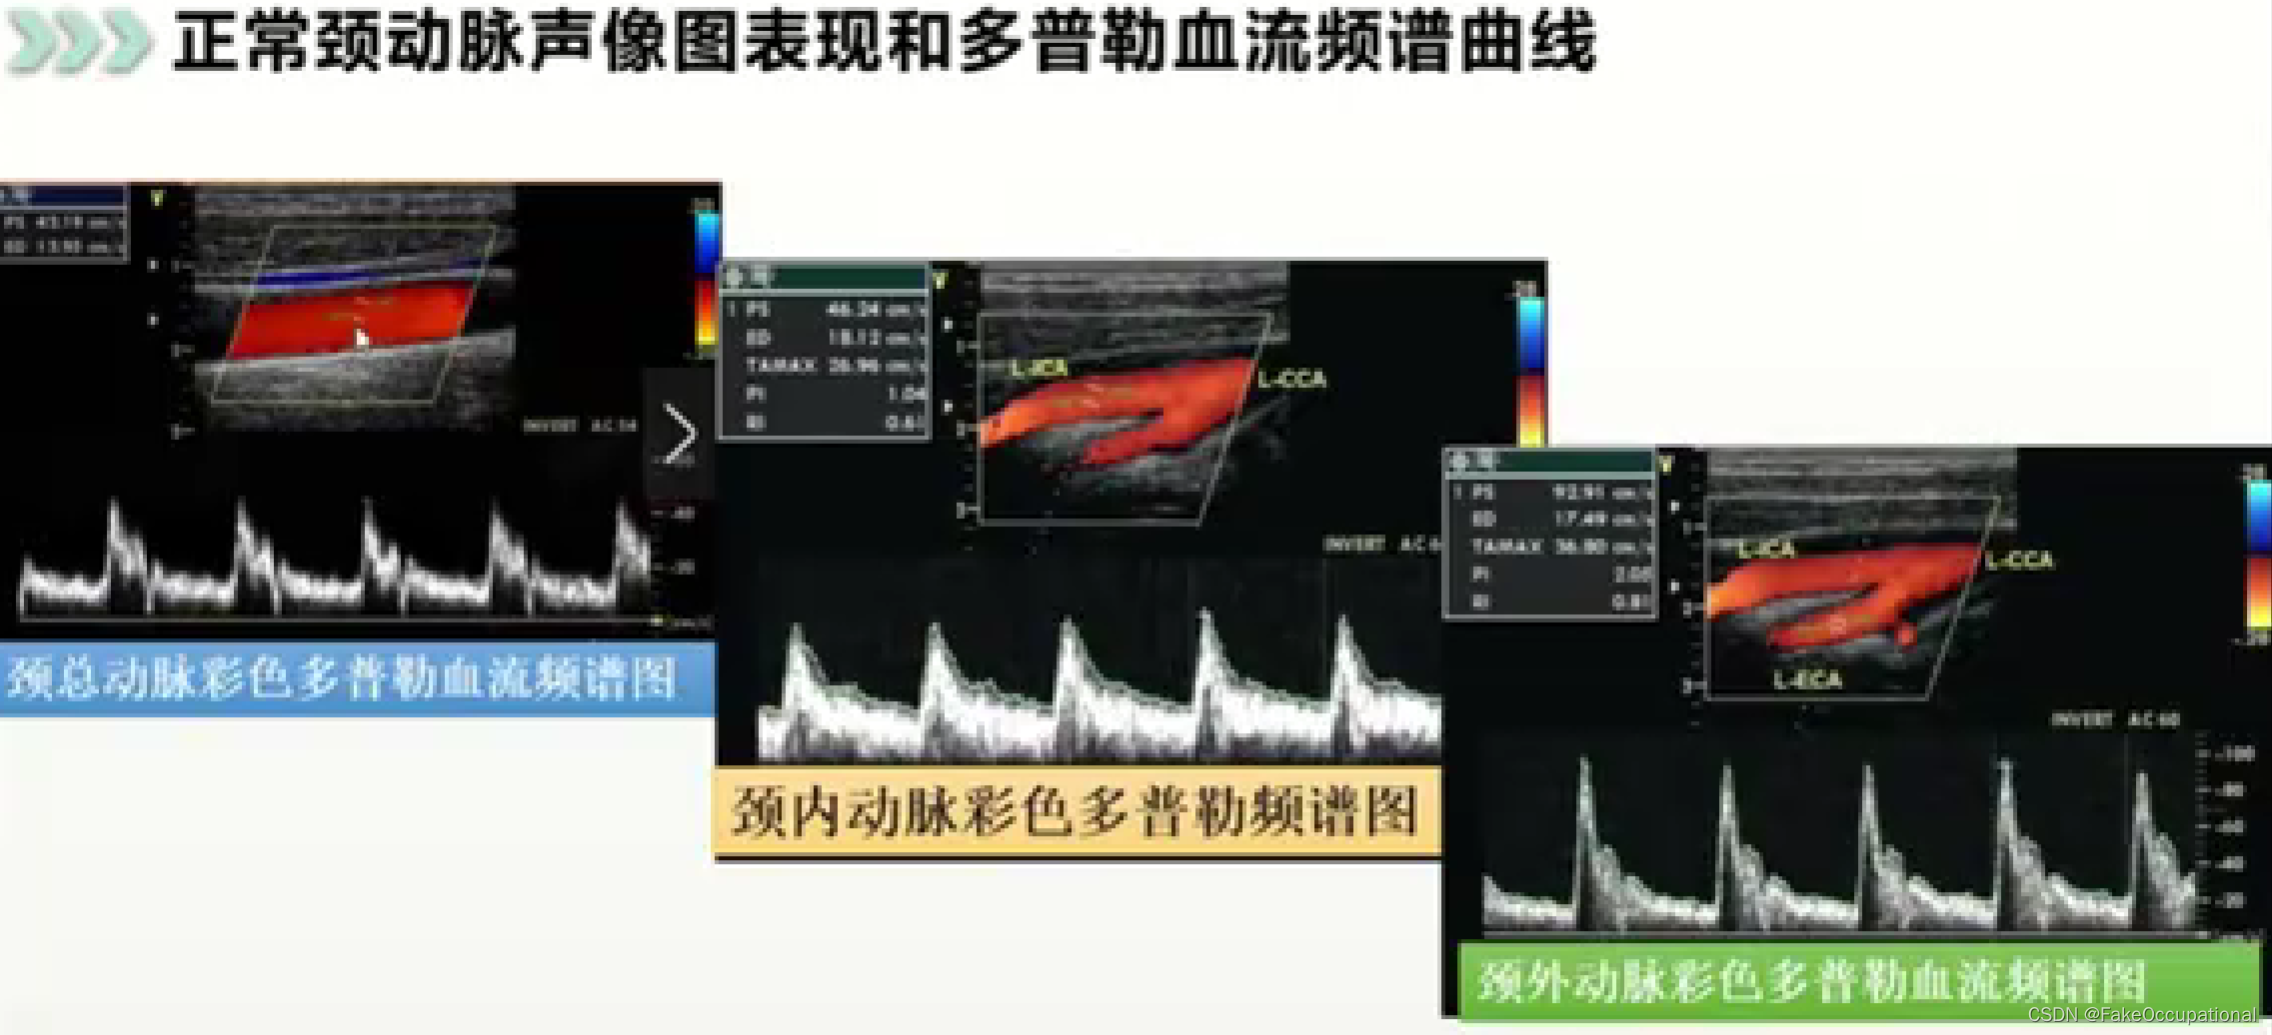

血管超声